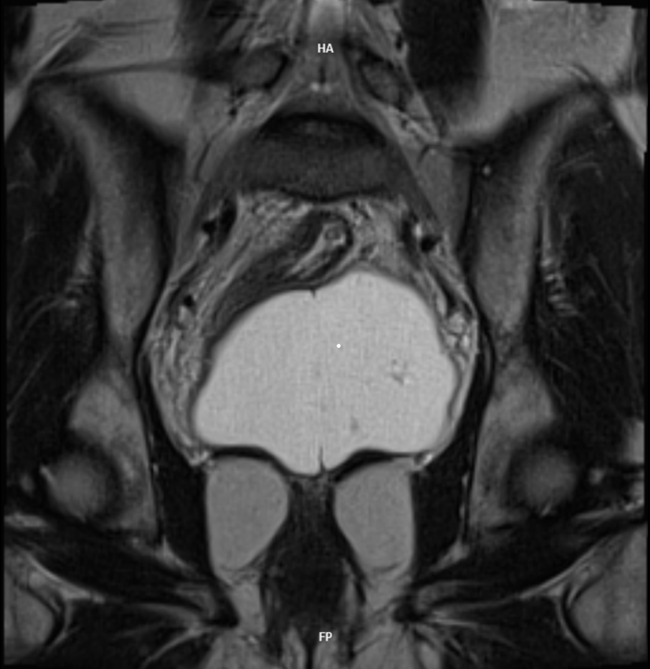

Xanthogranulomatous Pyelonephritis: An Uncommon Form of Pyelonephritis Highlighted in a Case Report

Danielle Malavazi Oliveira; Bárbara Sthefany de Paula Lacerda; Matheus Compart Hemerly, Maria Isabel Lima dos Santos, Weverton Machado Luchi